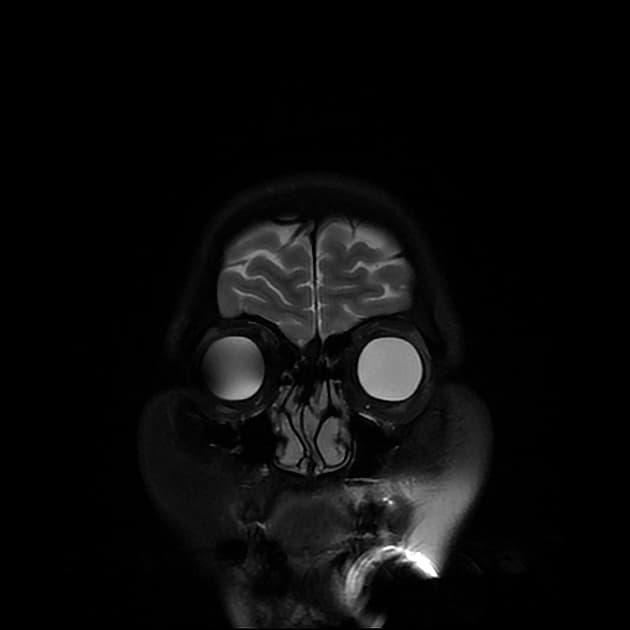

- Khối liên tục với cuống yên, làm giãn cuống này cả phía trên và phía dưới.

- Phù hợp với kiểu tăng quang đặc trưng và nằm trong cuống yên (infundibulum).

- Khối phù hợp với kiểu tăng quang đặc trưng và nằm trong cuống yên (infundibulum).

- Khối liên tục với cuống yên, làm giãn cuống cả phía trên và phía dưới.

- "Đặc điểm hình ảnh gồm khối u ranh giới rõ, tăng quang mạnh, liên tục với và làm giãn cuống yên."

U Pituicytoma là một loại khối u thần kinh đệm lành tính, phát triển chậm và hiếm gặp, xuất phát từ các tế bào pituicyte ở thùy sau tuyến yên hoặc cuống yên. Khối u thường biểu hiện như một tổn thương ranh giới rõ, tăng quang mạnh và liên tục với, đồng thời làm giãn cuống yên. Trên cộng hưởng từ (MRI), khối u thường có tín hiệu đẳng trên hình ảnh T1 và tăng quang đồng nhất sau khi tiêm thuốc cản quang. Việc không có dấu hiệu ác tính, không bệnh toàn thân và tổn thương ổn định dài hạn trên hình ảnh học làm tăng khả năng chẩn đoán u Pituicytoma, ngay cả khi chưa xác định bằng mô bệnh học. Các chẩn đoán phân biệt bao gồm u tuyến yên có liên quan đến cuống yên, u màng não và bệnh tổ chức bào Langerhans, những bệnh này có thể có hình ảnh tương tự. Tuy nhiên, vị trí đặc hiệu trong cuống yên và sự liên tục với cuống làm nghiêng về chẩn đoán u Pituicytoma. Điều trị thường mang tính theo dõi bảo tồn, đặc biệt ở bệnh nhân không có triệu chứng.